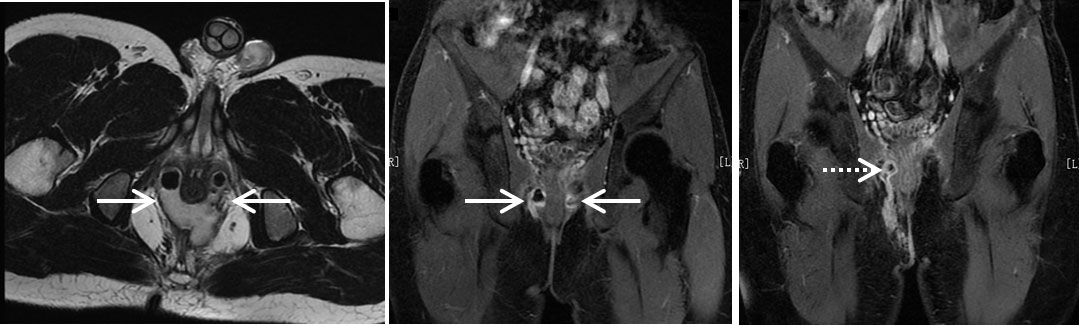

图2 克罗恩病肛瘘术前及术后MR检查 A:术前轴位T2加权成像示双侧耻骨直肠肌“后马蹄”脓肿(实箭),脓肿呈明显高信号,内见低信号积气影;B:术前冠状位增强检查见脓肿呈环形强化(实箭);C:术后2个月冠状位增强检查示左侧脓肿吸收,右侧脓肿复发并穿过肌肉达右侧坐骨肛门窝(虚箭)